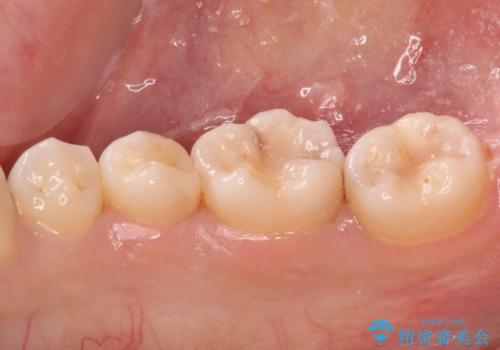

レントゲン写真などから、速やかに処置を行うべき歯が2歯あったため、それぞれセラミックインレーとPGAインレー(ゴールドインレー)にて修復治療を行うこととしました。

どちらの歯も痛みなどの症状はなく、治療後も異常所見なく経過をたどっています。

上顎大臼歯は向かい合った人から見えることはほとんどないため、切削量が少なく、適合の良いゴールドインレーが大変おすすめとなります。